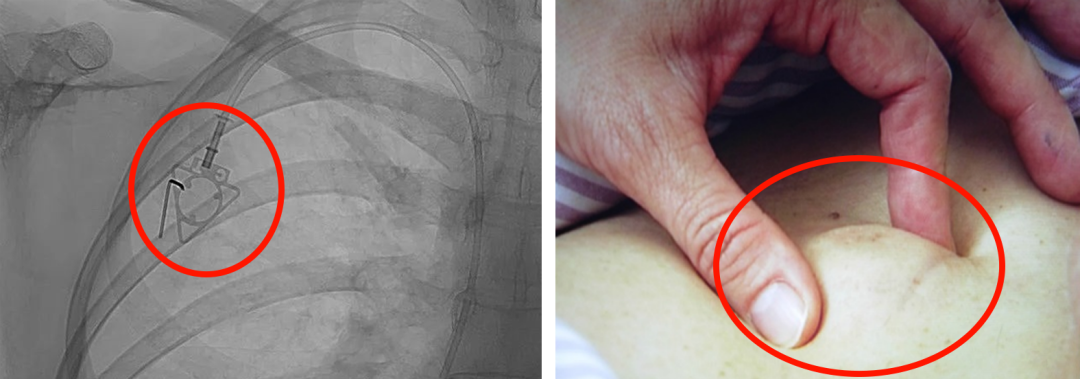

輸液港,臨床上也稱為PORT,是為了減輕藥物對患者血管刺激而置入體內(nèi)的專業(yè)輸液裝置。它分為三部分:無損傷針、置入靜脈的導(dǎo)管、埋藏在皮下與輸液針連接的注射座(港體)。注射座連接插入大靜脈的導(dǎo)管形成長期血管通路,發(fā)揮類似港口的作用,故稱作“輸液港”。

(1)輸液港輸注藥物直達(dá)大血管,手臂不會(huì)產(chǎn)生明顯的不適。由于每次穿刺的是皮下置入的港,可以減少針頭對血管的刺入次數(shù),操作簡單,對患者的血管起到保護(hù)作用;

(2)輸液港放置在皮下,不易被別人發(fā)現(xiàn),具有隱秘性;洗澡,日常生活不受限制;

(3)由于輸液港完全埋藏在體內(nèi),不易受到感染;